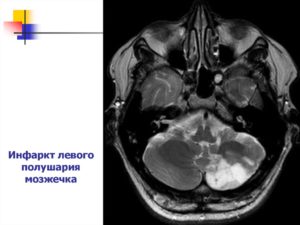

На долю инфаркта мозжечка приходится около 1,5% всех внутримозговых некрозов, в то время как кровоизлияния составляют десятую часть всех гематом. Среди инсультов именно мозжечковой локализации примерно ¾ приходится на инфаркты. Смертность высока и в иных случаях превышает 30%.

Ишемический инсульт мозжечка, или инфаркт, возникает по причине тромбоза или эмболии сосудов, питающих орган. Эмболия наиболее распространена у больных, страдающих сердечной патологией.

Изолированный инсульт участка гемисферы мозжечка, когда затронуто кровоснабжение из задней нижней мозжечковой артерии, проявляется комплексом вестибулярных расстройств, самым частым их которых является головокружение. Кроме того, больные испытывают боли в затылочной области, жалуются на тошноту и нарушение походки, страдает речь.

Инфаркты в зоне передней нижней мозжечковой артерии тоже сопровождаются расстройствами координации и походки, мелкой моторики, речи, но среди симптомов появляются нарушения слуха. При поражении правого полушария мозжечка слух нарушается справа, при левосторонней локализации – слева.

Если поражена верхняя мозжечковая артерия, то среди симптомов будут преобладать расстройства координации, пациенту сложно удерживать равновесие и выполнять точные целенаправленные движения, изменяется походка, беспокоит головокружение и тошнота, возникают сложности в произношении звуков и слов.

При крупных размерах очага повреждения нервной ткани яркая симптоматика расстройств координации и моторики сразу же наталкивает врача на мысль об инсульте мозжечка, но случается, что больного беспокоит лишь головокружение, и тогда в диагнозе фигурирует лабиринтит или другие заболевания вестибулярного аппарата внутреннего уха, а значит, правильное лечение не будет начато вовремя. При совсем небольших очажках некроза клиники может не быть вовсе, так как функции органа быстро восстанавливаются, но примерно четверти случаев обширных инфарктов предшествуют транзиторные изменения или «малые» инсульты.